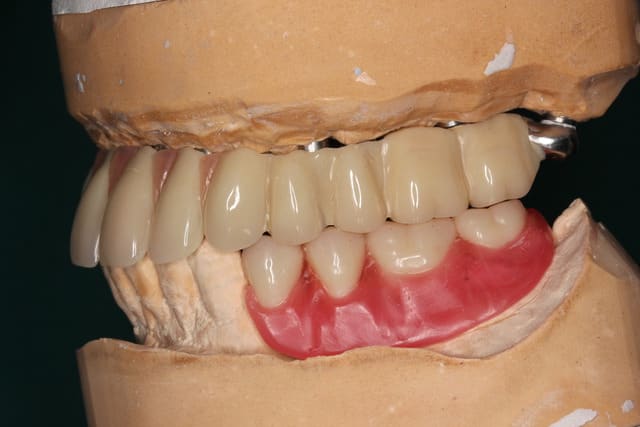

Img 1182 s6mmza - Eugenol

Img 1193 e1whny - Eugenol

Img 1194 xpaov4 - Eugenol

Manque que 6 e.max en antérieur !